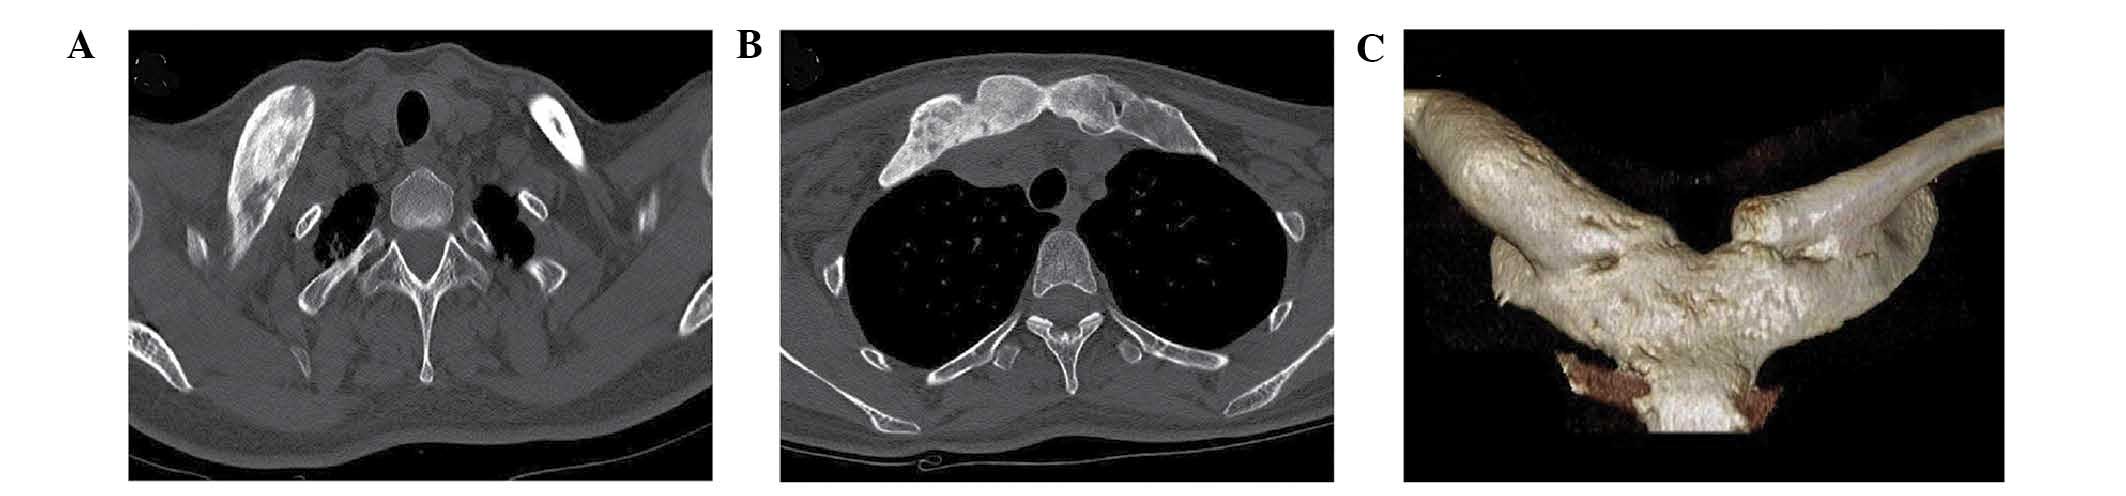

Whole-body 99m Tc methylene diphosphonate bone scintigram demonstrates increased uptake in both sternoclavicular joints the sternum the right greater trochanter. These diseases share some clinical radiologic and pathologic characteristics. It is composed of two portions separated by an articular disc of fibrocartilageThe bone areas entering into its formation are the sternal end of.

The sternoclavicular joint or sternoclavicular articulation is the joint between the manubrium of the sternum and the clavicle boneIt is structurally classed as a synovial saddle joint and functionally classed as a diarthrosis and multiaxial joint. B Bone scintigram obtained with technetium 99m 99m Tc medronate shows areas of increased radiotracer activity in the medial aspect of both clavicles arrows and in the. An entity initially known as chronic recurrent multifocal osteomyelitis was first described in 1972.

Especially the inspection of tonsillitis periodontitis and sinusitis is very important. These diseases share some clinical radiologic and pathologic characteristics. Joint Specific Conditions SAPHO Syndrome Middle-aged adults Skin changes ESRCRP mildly elevated Erosive changes Ossification of ligament insertion. Especially the inspection of tonsillitis periodontitis and sinusitis is very important. Treatment for focal infections. A Axial chest CT image shows marked hyperostosis osteosclerosis and ankylosis of the sternoclavicular joints arrows. SAPHO is an acronym for synovitis acne palmoplantar pustulosis hyperostosis and osteitis.